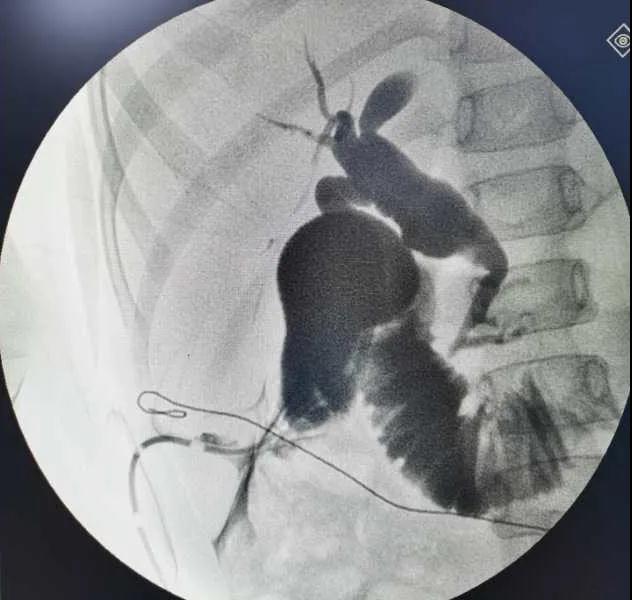

5月7日,西安國際醫(yī)學中心醫(yī)院小兒外科郭正團教授團隊成功為1名膽總管囊腫患兒進行了腹腔鏡膽管造影 腹腔鏡膽總管囊腫切除 腹腔鏡肝管空腸吻合術(shù)。目前,患兒恢復(fù)良好,已正常進食。

入院后,謝崇醫(yī)生積極為患兒完善術(shù)前準備,MRCP(核磁共振膽道水成像)顯示該患兒為膽總管囊腫Ic型,有明顯的胰膽合流異常。面對復(fù)雜的病情,小兒外科郭正團主任立即組織團隊進行術(shù)前討論,制定了完善的手術(shù)方案及應(yīng)急措施。

5月7日,一切準備就緒,郭正團主任主刀,帶領(lǐng)小兒外科團隊進行腹腔鏡膽管造影 腹腔鏡膽總管囊腫切除 腹腔鏡肝管空腸吻合術(shù)。術(shù)中,患兒膽總管與周圍肝動脈及門靜脈粘連嚴重,給手術(shù)增加了難度。郭正團主任沉著冷靜,操作嫻熟,完整剝離了膽總管囊腫及遠端胰腺段膽管,肝總管與空腸完成了Roux-en-Y吻合,手術(shù)進行順利。術(shù)后第2天,玲玲就可以下床活動;第6天,已正常飲食。